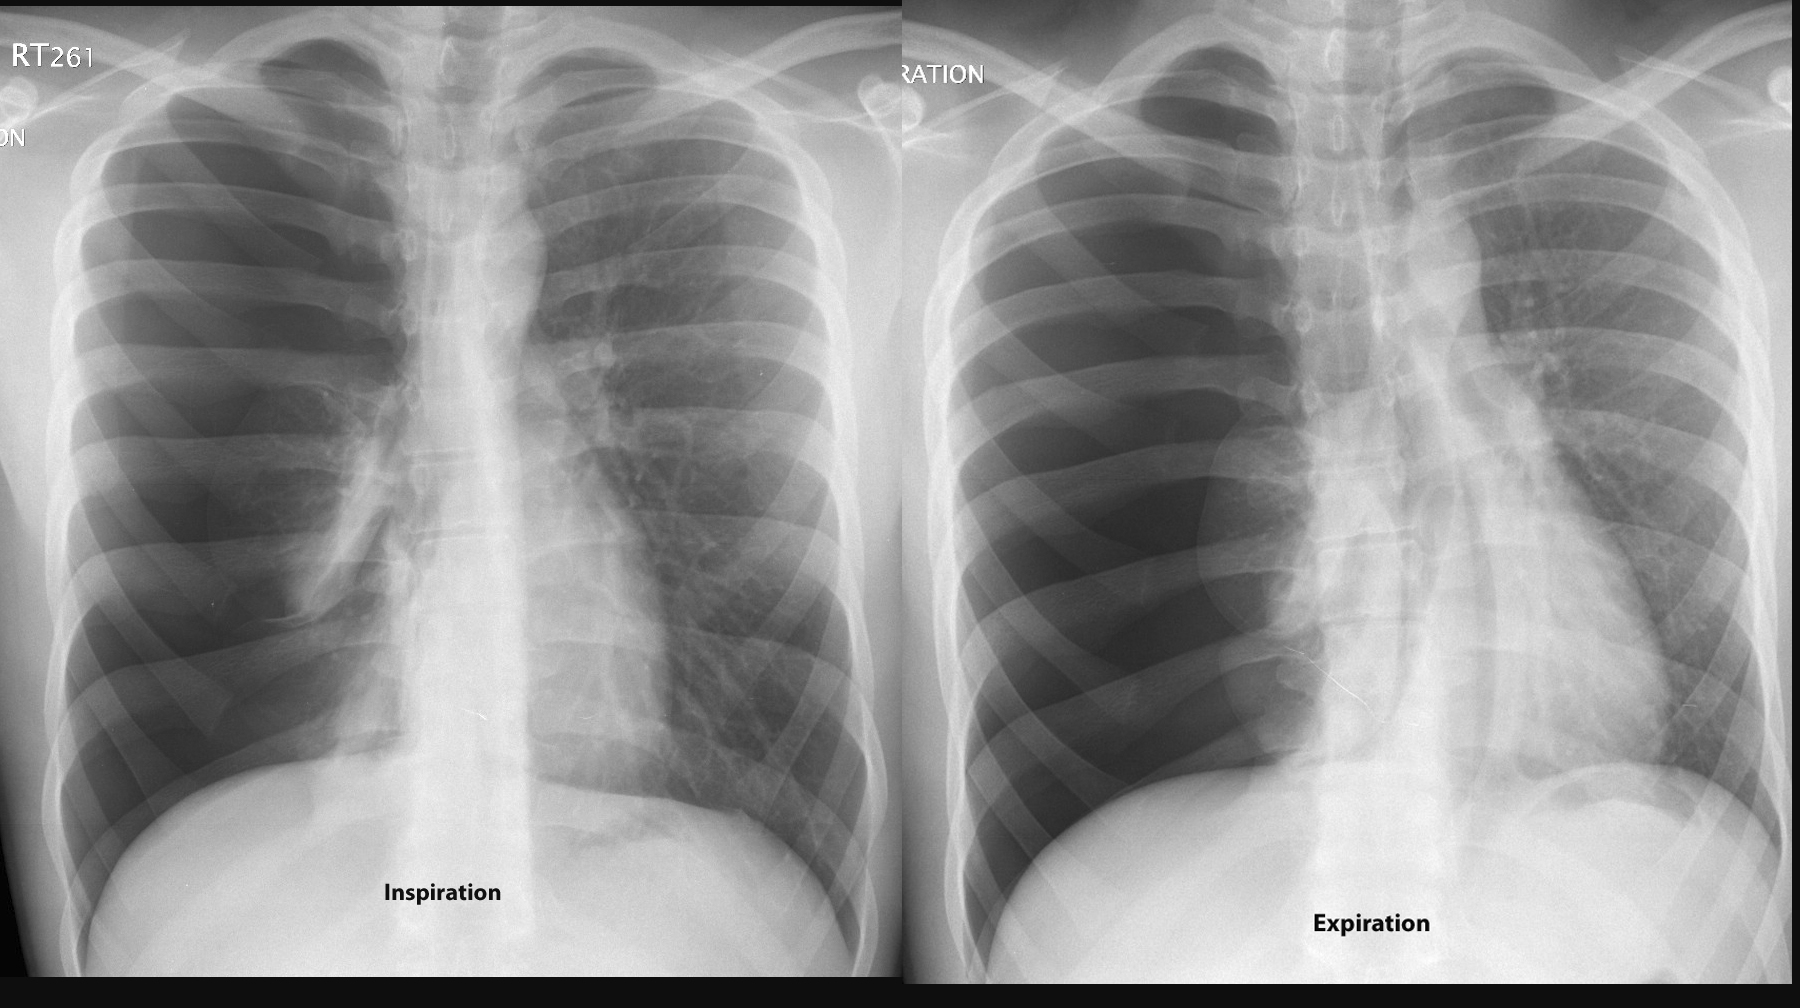

Pneumo insp/exp

(similar - mild tension)